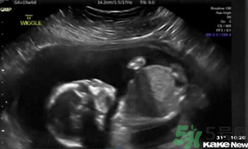

還只有5個(gè)月半的胎兒居然自己打自己的臉,這也太奇葩了,將來(lái)可能是個(gè)拳王啊。~美國(guó)堪薩斯州一個(gè)5個(gè)月半大的胎兒在母親子宮內(nèi)打自己的臉并把自己擊倒,這一幕剛好被父母用超聲波檢測(cè)儀記錄了下來(lái),并被分享到網(wǎng)上,引得眾人稱(chēng)奇。這對(duì)夫婦原本還擔(dān)心兒子可能會(huì)有腦震蕩,但護(hù)士讓他們放心。凡妮莎說(shuō),這次的事件導(dǎo)致他們開(kāi)始考慮兒子的個(gè)性:“我們倆都愛(ài)終極格斗。所以我們正在討論他或許會(huì)成為一個(gè)拳擊手?!?/p>